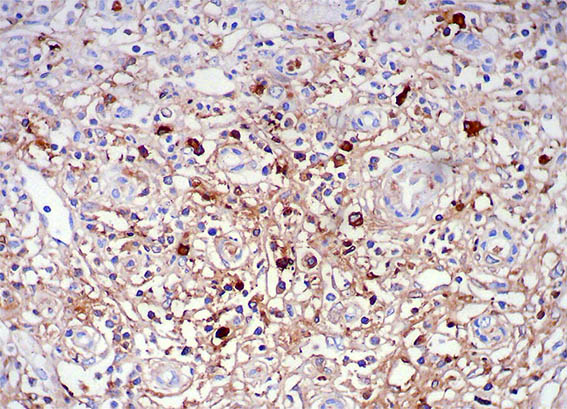

Figure 11. Immunohistochemistry for IgG4, X200.

Figure 12. Immunohistochemistry for IgG4, X400.